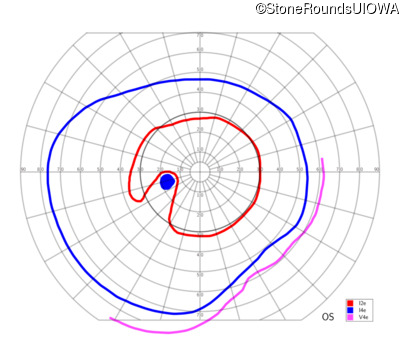

AD CSNB (IA2fii)

AD CSNB (IA2fii)